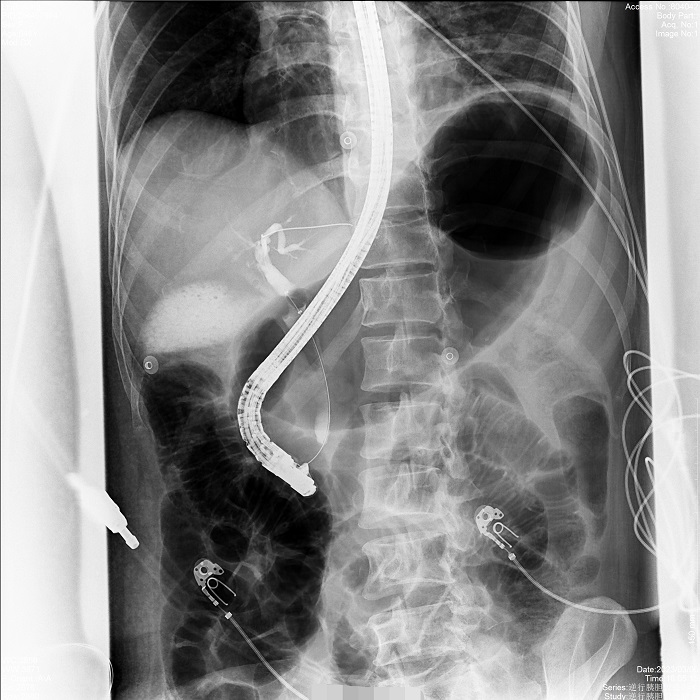

病例2:患者間歇性上腹部脹痛不適2年,MRCP示膽總管明顯擴(kuò)張,膽囊多發(fā)結(jié)石,醫(yī)生決定應(yīng)用ERCP的手術(shù)方式解除膽道梗阻,通暢引流。在普利德多動能動態(tài)平板DRF上進(jìn)行ERCP應(yīng)用,成功取出全部結(jié)石,術(shù)后觀察膽汁引流通暢,患者病情平穩(wěn)。